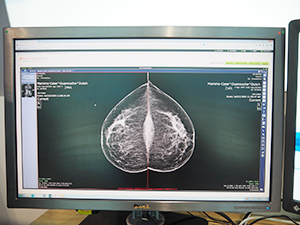

今回の展示テーマの1つである“Universal Viewing & Sharing”については,Webベースのブラウザ上で動作するビューワであるiNteract+ iEMVにより,院内・院外におけるゼロフットプリント環境で,DICOM,非DICOMデータを参照するというソリューションを紹介した。iNteract+ iEMVの新バージョンの特長としては,ユーザーインターフェイスを見直し,メニューバーを上部から右側に移したことである。これにより,PCだけでなくタブレットやスマートフォンから画像を参照する際にも画像の表示エリアが拡大し,より視認性に優れた参照環境を提供する。米国では,Epic社の電子カルテシステムと組み合わせて,カルテ画面上から画像参照ビューワとして起動するといった連携を行っている。日本国内でも同様に電子カルテシステムと連携させることで,効率的な画像参照を行うことが可能である。また,iNteract+ iSHAREは,異なる医療機関間での情報共有・連携を行うためのソリューションである。iNteract+ iSHAREのリスト画面から共有したいデータを選択し,インターネットを介して依頼すると,依頼先施設はiNteract+ iEMVを用いて依頼元施設のサーバなどに保存されている画像を参照することができる。

ゼロフットプリント環境でブラウザベースで |